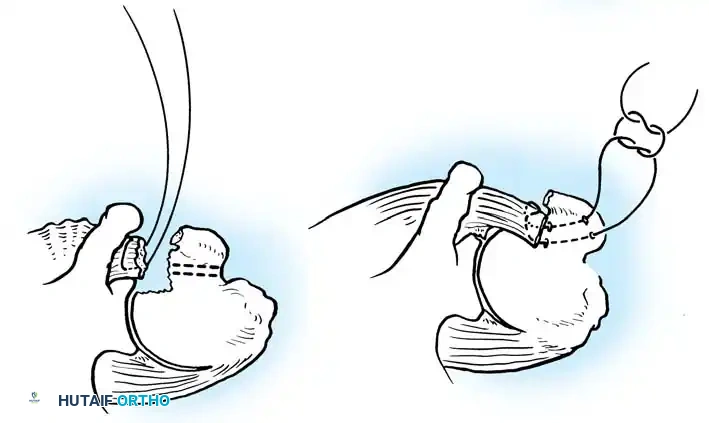

Glenoid Preparation and Labral Repair

The essential step in restoring stability is the anatomical reduction of the capsulolabral complex to a bleeding bone bed on the anterior glenoid rim.

- Debridement: The anterior glenoid neck is decorticated using a motorized burr, rasp, or osteotome to create a bleeding cancellous bed. This promotes robust biological healing of the repaired labrum.

- Mobilization: The scarred, medially displaced labrum (ALPSA lesion) must be fully mobilized using a periosteal elevator until the subscapularis muscle belly is visible anteriorly. The tissue must float freely to be shifted superiorly and laterally.

- Anchor Placement: Suture anchors (typically 3 to 4) are placed along the articular margin of the anteroinferior glenoid (from the 5:30 to 3:00 positions for a right shoulder). Anchors must be inserted at a 45-degree angle to the articular surface to maximize pullout strength and avoid joint penetration.